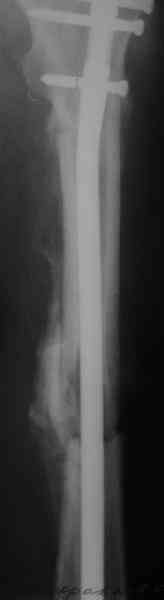

Вот несколько. С тисками и трубой на днях сделаем.

> Вот несколько. С тисками и трубой на днях сделаем.

Саша, последний штифт, пожалуй, перегнули?

> Саша, последний штифт, пожалуй перегнули?

Там заход сделан как для прямого штифта, не через вертел.